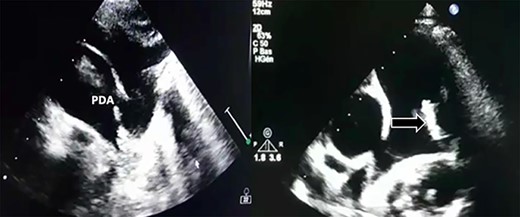

Transthoracic echocardiography revealed a large PDA (10 mm) with left-to-right shunt and a fixed structure on the wall of the pulmonary artery, with erratic movement indicative of a vegetation (Fig. 1), and mobile vegetation attached to the wall of the descending aorta in the supra-sternal view (Fig. 2) and a left ventricle with conserved systolic function and 55-mm end-diastolic diameter.

Large PDA and a fixed structure on the wall of the pulmonary artery.

Supra-sternal view: vegetation attached to the wall of the descending aorta.